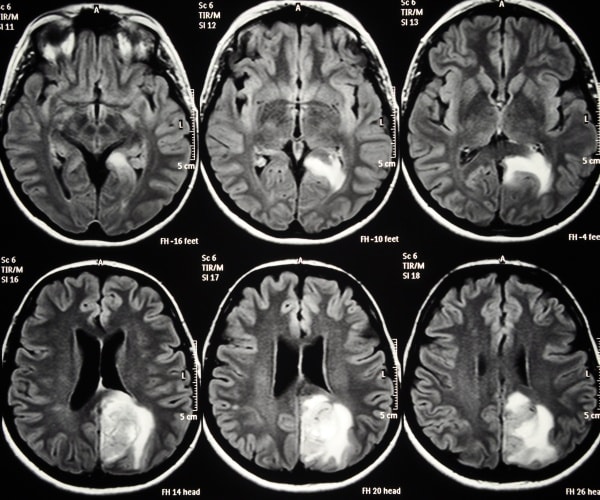

x-rays of brain with glioblastoma

(Dreamstime)

Glioblastoma is a very deadly cancer, with an average survival of around 15 months. Currently, doctors use surgery, radiation and chemotherapy to fight the tumor.